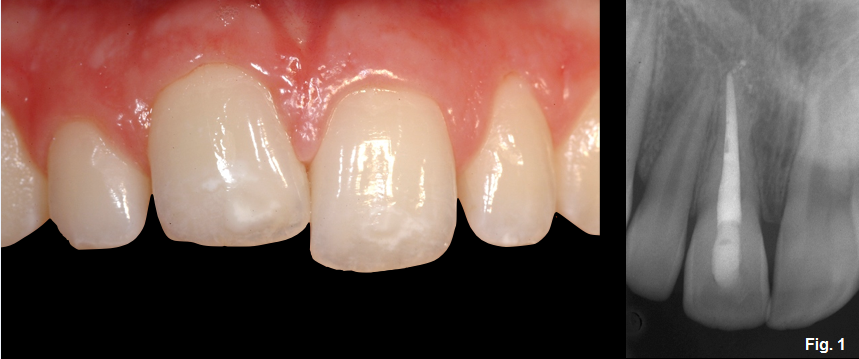

Fig. 1 shows a female patient who presented to the office at the age of 15 with tooth #8 ankylosed. This tooth was avulsed when she was 11 years old and reimplanted after being out of the mouth for approximately one hour. The desire of the patient and her family was to improve the esthetics. As you can see, the incisal edge and gingival margin are more apically positioned, compared with the adjacent teeth.